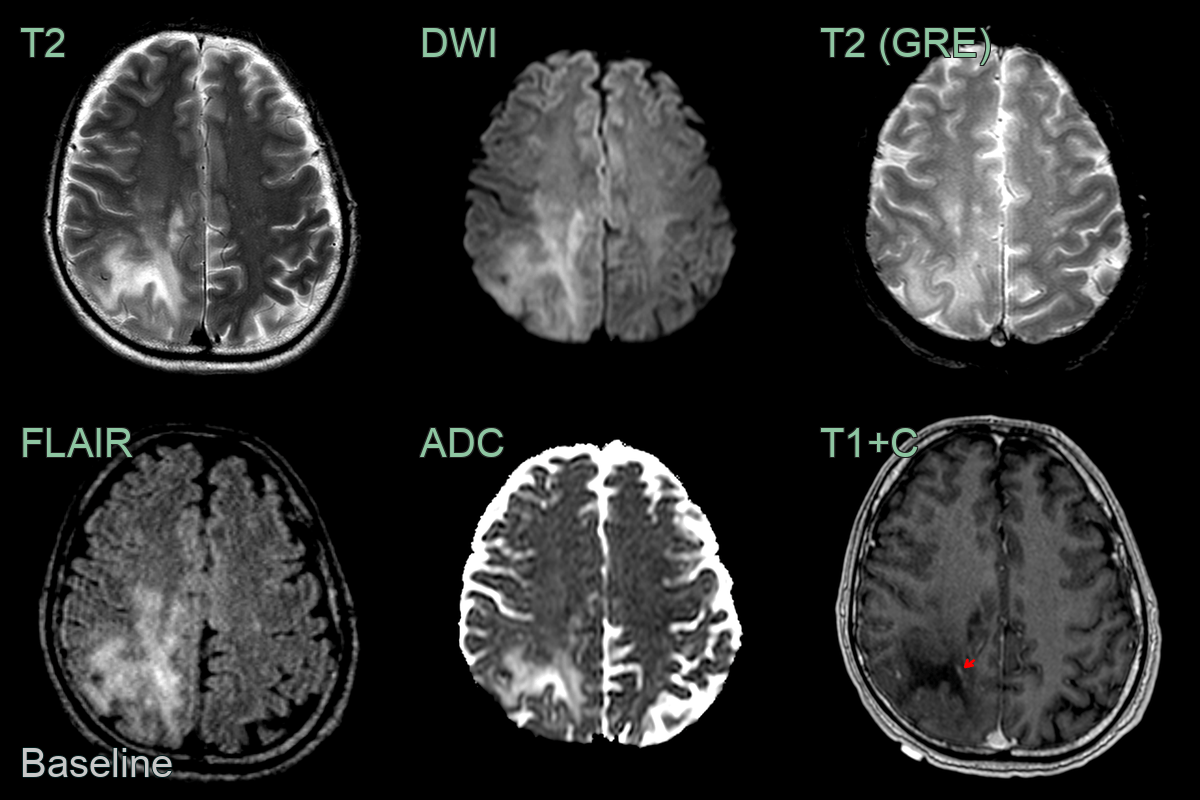

- 70-year-old patient undergoing treatment for lymphoma. Presented with seizures, confusion, and aphasia.

- MRI showed peripheral FLAIR-hyperintense and T1-hypointense lesions extending up to the cortex with no mass effect or enhancement.

- After one month and treatment with pembrolizumab, the lesions had enlarged with a more obvious leading edge of diffusion weighted hyperintensity. There was no contrast enhancement to suggest PML-IRIS.